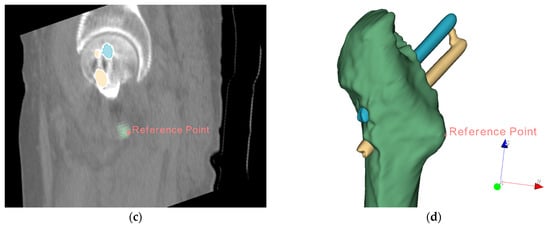

The fixed image and floating image after fine registration are shown in Figure 10. In the two CT images after alignment, the proximal femur parts without the femoral head are overlapped and served as the reference. Observed in 3D space, the proximal pin and distal pin are in the same spatial coordinate system, and after 3D reconstruction, the voxel data of pins in CT are transformed into point cloud data, as shown in Figure 11.

Figure 10.

CT images after registration: (a) fixed images; (b) fine-aligned floating images; (c) the two images in the coordinate system with the overlapping femur as the reference.

Figure 11.

3D point clouds of proximal pins and distal pins in the same spatial coordinate system for both previous and posterior CT images. The purple point cloud is part of the proximal femur and pelvis. The green and blue point clouds represent the proximal and distal pins obtained from the first postoperative CT scan. Gold and red point clouds represent the proximal and distal pins from the second CT image after the previous CT scan, respectively.